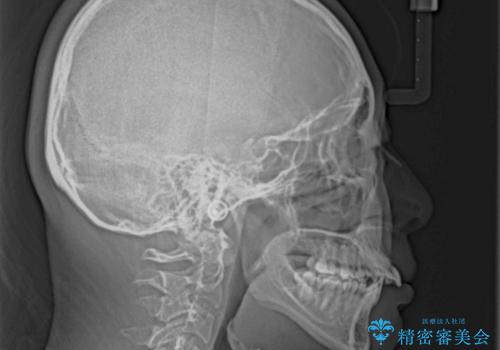

- 咬み合わせと、前歯のデコボコや八重歯、飛び出した口元を気にして来院された患者様です。

上顎は歯列不正が強く、右側臼歯部の咬み合わせは歯1本分ずれている状態でした。

補助装置を用いて奥歯の咬み合わせを改善しながら歯列を後方に移動させ、上下左右第一小臼歯を4本抜歯することで八重歯や口元の突出感を改善することとしました。

奥歯の咬み合わせの不正が顕著であったため、表側のワイヤー装置を選択して矯正治療を行うこととしました。